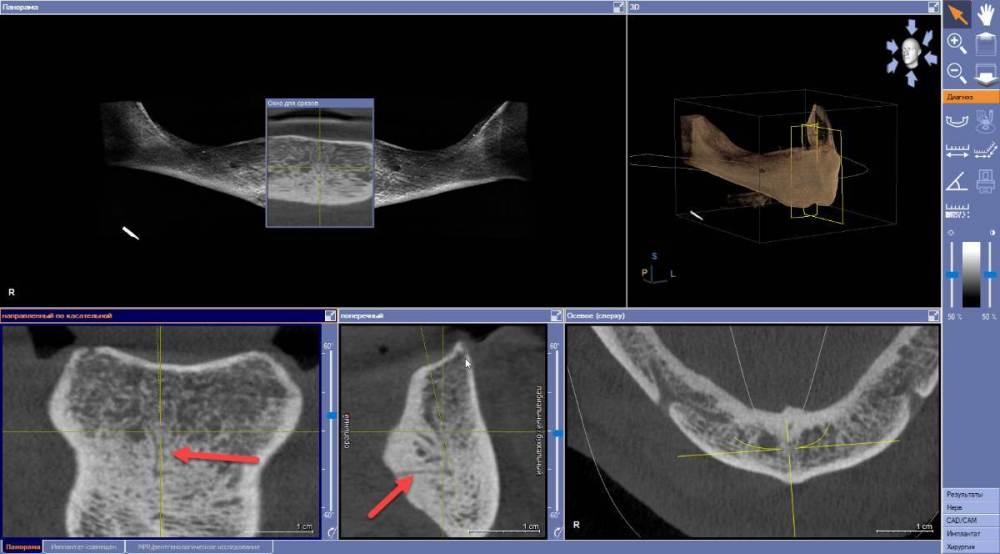

Estes Опубликовано 6 апреля, 2022 Автор Поделиться Опубликовано 6 апреля, 2022 Здравствуйте. Вот подошел ко мне пациент с полной адентией на в/ч и н/ч. На в/ч ПСП держится нормально, на н/ч - не носит. Подскажите - установка 4х имплантов 44-42-32-34 и дальнейшее протезирование например съемным на балке тут показано? Есть ли необходимость сравнять гребень во фронтальном отделе? Соотношение челюстей в целом таково, что места весьма прилично для съемника на балке. Еще подскажите, какие осложнения могут в принципе быть при установке импланта в резцовую ветвь - у пациента что-то они выражены? И вот что за трещинки в теле челюсти язычно - на фото стрелками показал ? 2022-04-06_08-22-32.mp4 Ссылка на комментарий

Irouil Опубликовано 6 апреля, 2022 Поделиться Опубликовано 6 апреля, 2022 Трещинки - мелкие сосуды Осложнения обычные - кровотечения в процессе операции, болевой синдром в случае развития неврита - после Ссылка на комментарий